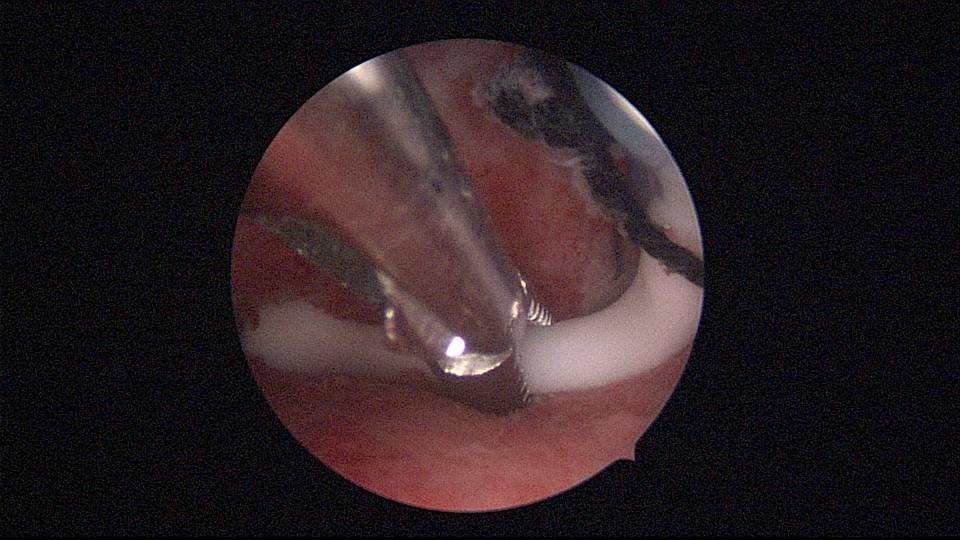

患者40岁,G0P0,原发不孕10+年,20+岁严重痛经,多家医院行腹腔镜手术治疗腺肌症合并多发性肌瘤,宫腔镜切除内膜息肉,前后肌注GnRH-a6针,痛经明显缓解。2017年试管助孕一次,失败,放弃生育需求,现要求放置曼月乐环并固定。2024年5月行宫腔镜下曼月乐不锈钢挂钩固定,子宫前位,宫深7cm,宫腔形态正常,宫内膜正常,双侧输卵管开口可见,将曼月乐环用4号丝线与挂钩连接并固定于宫底(第一次做宫腔镜下节育环固定,没有想到利用曼月乐尾丝连接环)。2024年6月复查B超,曼月乐固定装置扎入宫底肌层0.46cm,环位置正常,2025年5月复查B超,曼月乐顶端距宫底1.5cm。